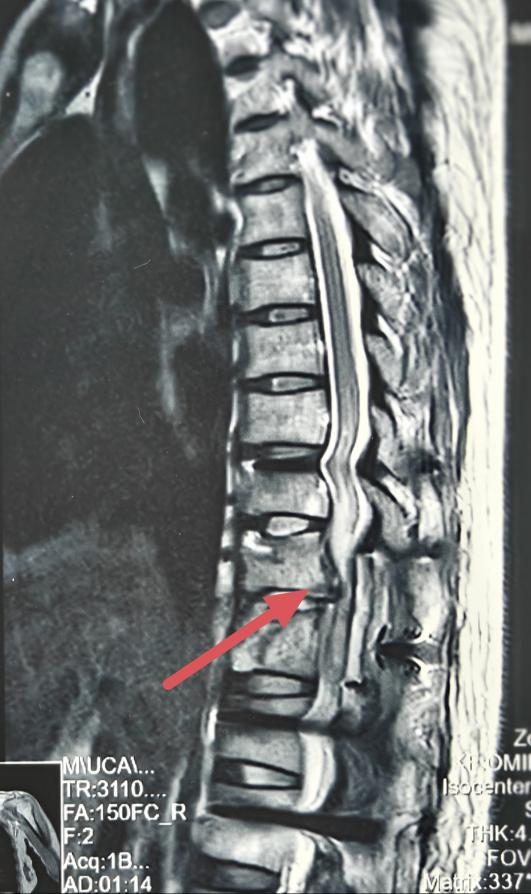

患者,女,2025年5月,不慎从4米高处坠落,伤后立即下肢瘫痪且失去知觉,伴近事遗忘,就近送往当地医院,检查提示胸11骨折伴脊髓损伤,头部CT提示脑挫伤,入院后给与对症治疗,脑挫伤改善后于伤后第七天行胸椎骨折复位内固定+椎管减压手术,术后持续下肢瘫痪,感觉及运动消失,大小便无知觉。

入院检查:神志清楚,肚脐以下感觉消失,下肢肌力0级,肌张力消失,下肢病理反射、生理反射均未引出,可引出肛门收缩,留置导尿。诊断:胸10-11脊髓损伤(ASIA B级),截瘫,神经源性膀胱,神经源性肠道。

图片图片

复位前MRI

复位后MRI